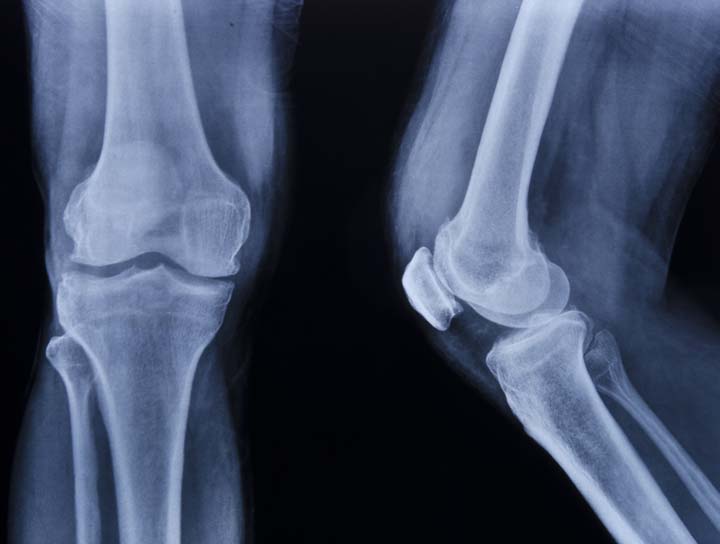

Osteoarthritis

Osteoarthritis is due to Wear and Tear of the cartilage.

With age our cartilage loses the resilience and undergoes degeneration.